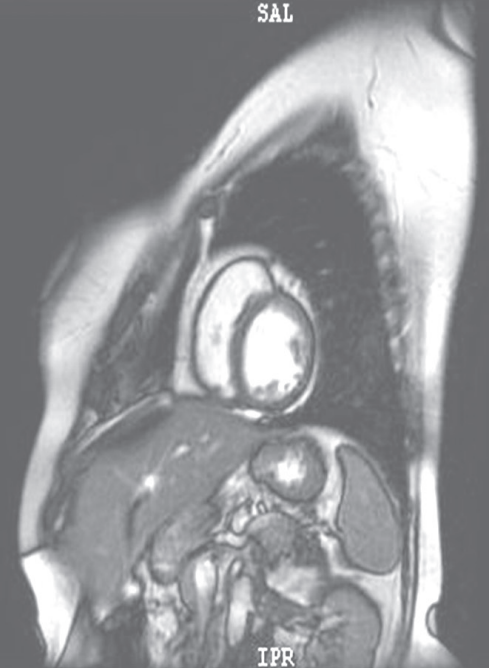

摘要:關(guān)于擴張性心肌病的最新治療,小巷深處的隱藏寶藏正逐漸為人們所發(fā)現(xiàn)。通過先進的醫(yī)療技術(shù)和方法,擴張性心肌病的治療取得了新的進展。這些治療方法旨在改善心臟功能,提高患者生活質(zhì)量。小巷深處的醫(yī)療機構(gòu)或?qū)<铱赡茈[藏著寶貴的治療經(jīng)驗和方法,為尋求最佳治療方案的病患帶來希望。更多詳細信息需要進一步探索和研究。